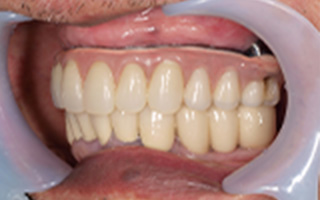

Before

After

| 55歳 男性 | |

|---|---|

| 主訴 | 前歯でしか咬めなく、食事を摂るのに非常に困難で辛い |

| 処置内容 | 上顎6本、下顎3本 |

| 治療費用 | 上顎: 約230万(税込) 下顎: 約120万(税込) |

| 治療期間 | 上顎: 1年(仮歯まで8ヶ月) 下顎: 8ヶ月(仮歯まで5ヶ月) |

| リスク | 上部構造物、仮歯の破折、術後の腫れ(3日)、人工歯根脱落リスクがあります |